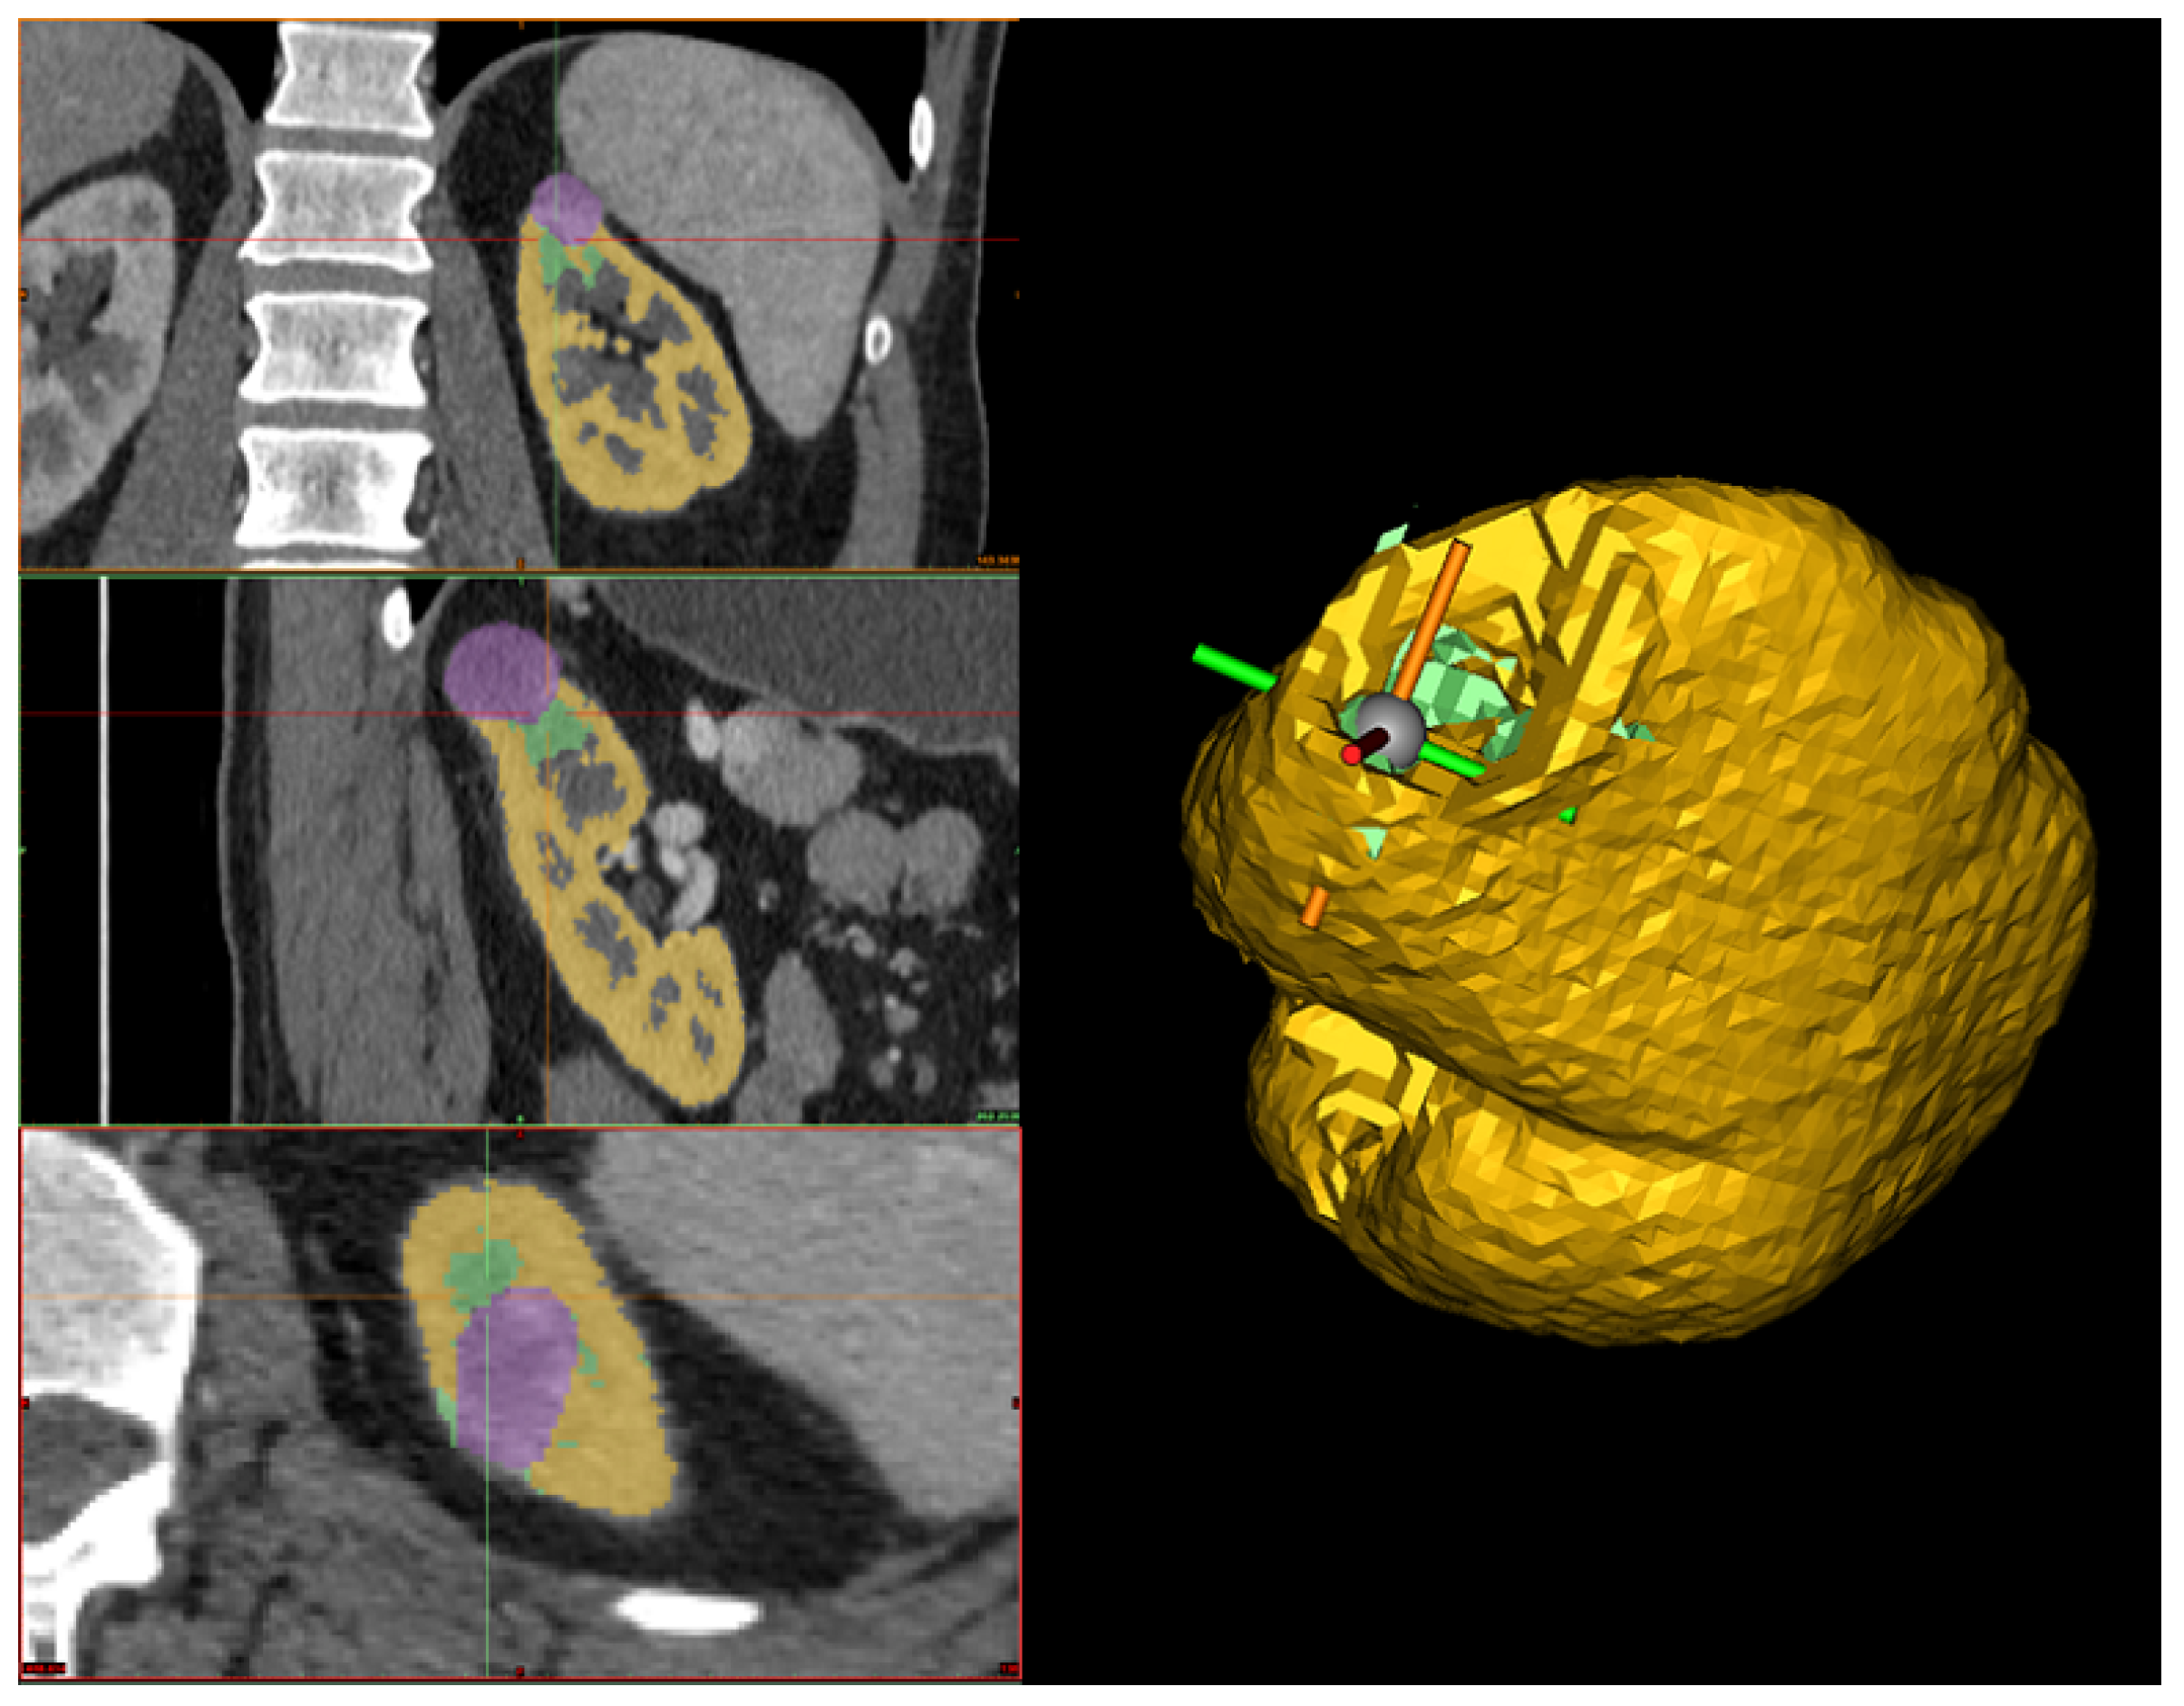

Therefore, the first step in correcting the reconstruction is to remove any tumor parts mistakenly considered part of the organ during kidney segmentation. Then, the human operator should inspect the interface between the tumor and the kidney to confirm the absence of gaps. If any holes are present, the Fill command is used to address them while checking each slice across the three sections (see Figure 6). Finally, before exporting the 3D models, a smoothing operator is applied to slightly refine the geometries of the two volumes. The final result can be seen in Figure 1, which was obtained from a combination of automated and manual tumor and organ segmentation. As previously discussed, organ and tumor segmentation is fundamental for the algorithm presented in Section 2.2. Here, we described a manual procedure for this segmentation. However, in the future, this could be replaced with a fully automated process.

Figure 6. On the left, the hole-filling process across the three different planes is shown, where the purple represents the tumor, the yellow represents the kidney, and the green indicates the manually filled region used to close the gap between the tumor and the kidney. On the right, the 3D reconstruction of the kidney after the filling process is displayed, where the yellow represents the kidney, and the green corresponds to the filled part of the kidney.